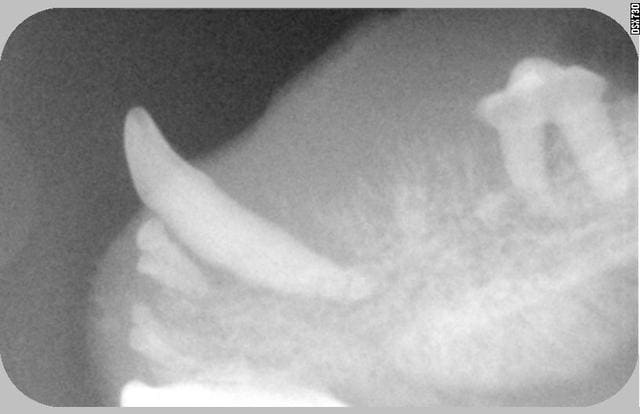

Effectivement c'était mon chat, la tumeur était trop importante pour être traitée chirurgicalement et la chimio trop lourde pour une chatte de 17 ans passé quand elle n' a plus réussi à s'alimenter j' ai été fort tristement obligée de la faire euthanasier.